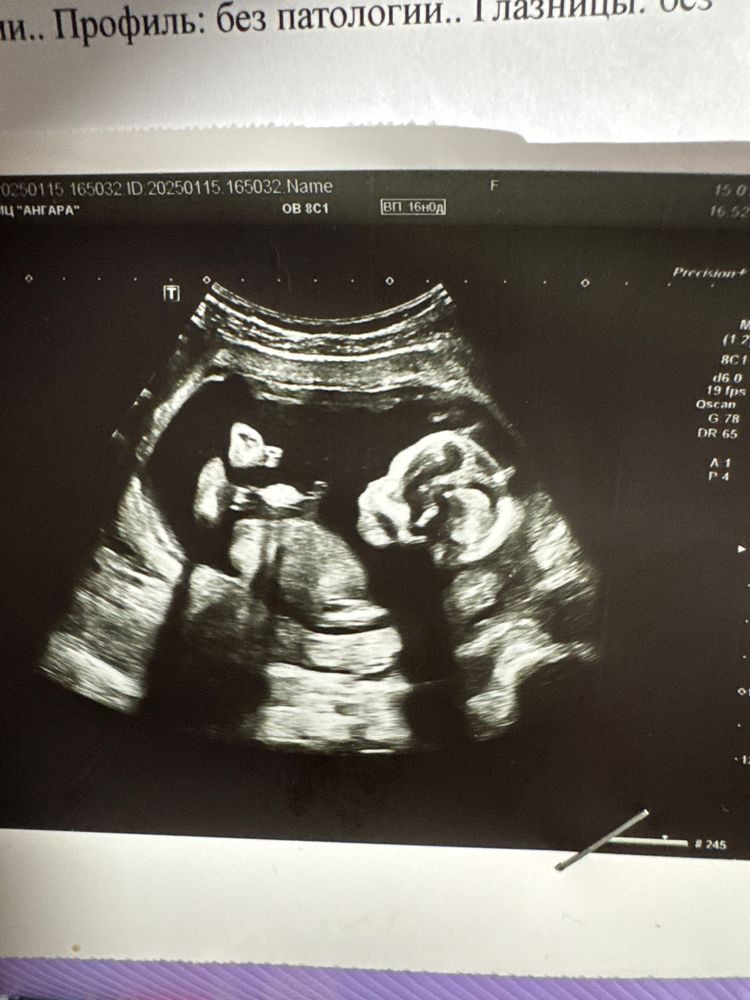

На фото 13 и 16 недель, уже есть сыночек, очень интересно кто второй, на днях второй скрининг 🙏🏼 подскажите по половому бугорку если видно, и совпало ли у кого? Могут ли перепутать девочку с мальчиком?

Не видно полового бугорка ☺️ В 16 недель уже между ножек смотрят.

А вам в 16 недель не сказали? С 16 недель уже в большинстве случаев хорошо видно. Мне и в 13 и в 16 сказали и в 21 ничего не изменилось